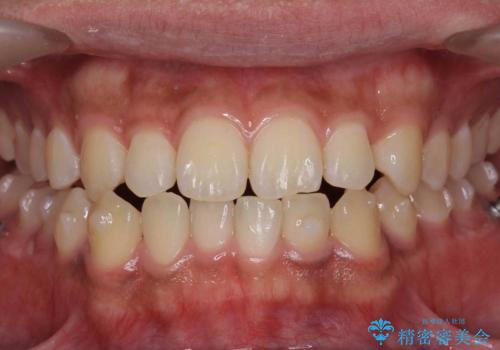

骨格性の受け口 非抜歯で下の歯を後ろに下げる インビザラインで インプラント矯正

- 受け口を主訴に来院。

他院でマウスピース矯正を始めたが、担当医に不信感をもち転院。

治療により受け口が改善し、下あごの輪郭も若干後ろに下がった印象になりました。

当院では下の歯を後ろに下げるため矯正用ミニスクリューを用いてしっかり移動を行う等ご説明をし、治療開始しました。